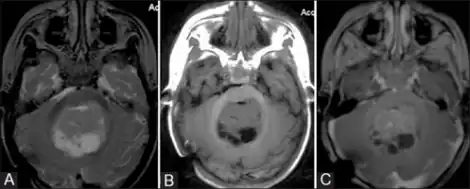

a) Female with atypical teratoid rhabdoid tumor axial T2 W image shows mixed solid–cystic lesion in midline b) axial T1W image shows isointense solid component c) axial T1W post-contrast image showing moderate enhancement of solid component

The initial diagnosis of a tumor is made with a radiographic study (MRI[20] or CT-). If CT was performed first, an MRI is usually performed as the images are often more detailed and may reveal previously undetected metastatic tumors in other locations of the brain. In addition, an MRI of the spine is usually performed. The AT/RT tumor often spreads to the spine. AT/RT is difficult to diagnose only from radiographic study; usually, a pathologist must perform a cytological or genetic analysis.

The tumors' appearance on CT and MRI are not specific, tending towards large size, calcifications, necrosis (tissue death), and hemorrhage (bleeding). Radiological studies alone cannot identify AT/RT; a pathologist almost always has to evaluate a brain tissue sample.

The increased cellularity of the tumor may make the appearance on an uncontrasted CT to have increased attenuation. Solid parts of the tumor often enhance with contrast MRI finding on T1 and T2 weighted images are variable. Precontrast T2 weighted images may show an isosignal or slightly hypersignal. Solid components of the tumor may enhance with contrast, but not always. MRI studies appear to be more able to pick up metastatic foci in other intracranial locations, as well as intraspinal locations.